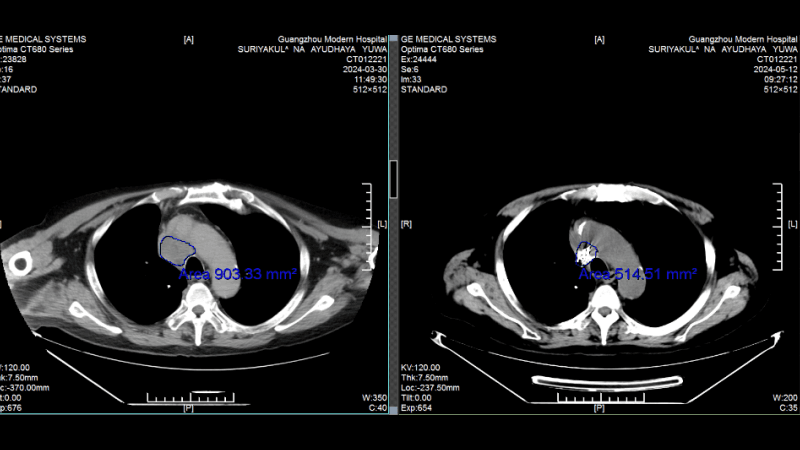

Сравнение КТ лёгких до и после лечения. Опухоль лёгких практически инактивирована

(Слева: до лечения, справа: после лечения)

Лечение дало ошеломляющие результаты: • После двух процедур КТ показало уменьшение очага в легком, а колоноскопия - значительное сокращение опухоли в кишечнике. • Исчезли мучительные симптомы: кашель и кровавый стул. • После семи сеансов опухоль в легком была практически полностью инактивирована, а в кишечнике - уменьшилась на 90%. Путь не был усыпан розами. Однажды у Радика резко упал уровень тромбоцитов, что грозило опасным кровотечением. В момент отчаяния именно настойчивость и профессионализм его лечащего врача, доктора Аденана, и всей команды спасли ситуацию. Быстро проведенная симптоматическая терапия стабилизировала состояние, и лечение было продолжено.